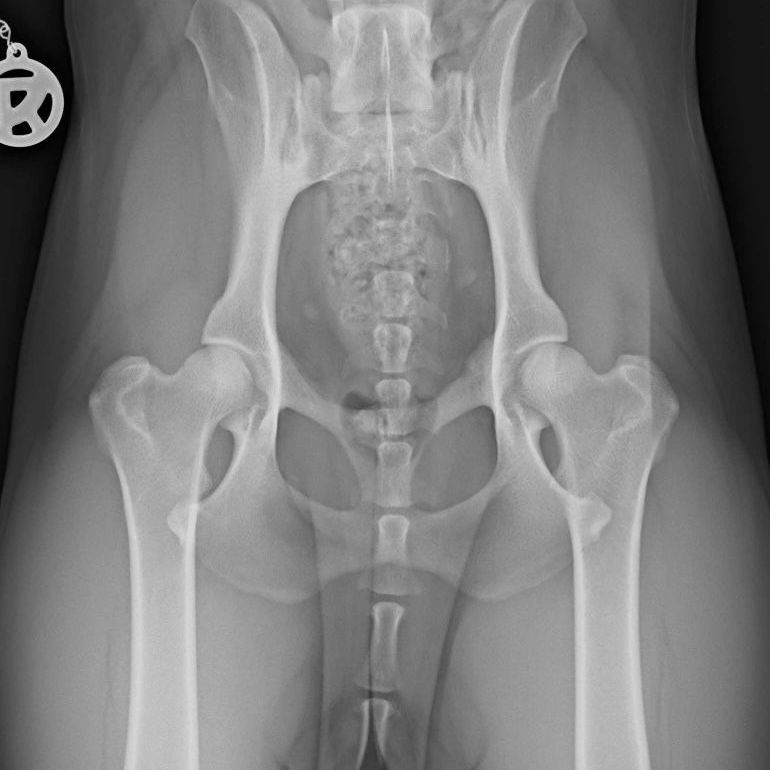

Außerdem geht man davon aus, dass z.B. eine Hüftgelenksdysplasie (HD) durch die damit einhergehenden Stellungsveränderungen der Gliedmaße oder auch Übergewicht, die mechanische Belastung erhöht und so den degenerativen Prozess begünstigen können.

Der Tierarzt kann den Kreuzbandriss durch den sogenannten Schubladen- oder den Tibiakompressionstest feststellen, sollte dies noch nicht zur vollständigen Klarheit führen, so müssen bilgebende Verfahren (Röntgen, CT, MRT) hinzugezogen werden.